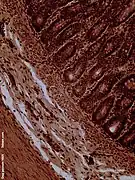

Histology

The jejunum contains very few Brunner's glands (found in the duodenum) or Peyer's patches (found in the ileum). However, there are a few jejunal lymph nodes suspended in its mesentery. The jejunum has many large circular folds in its submucosa called plicae circulares that increase the surface area for nutrient absorption. The plicae circulares are best developed in the jejunum.

• The villi of the jejunum look like long, finger-like projections, and are a histologically identifiable structure.